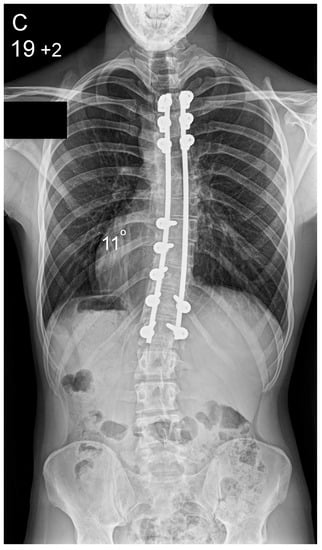

Figure 1.

Patient aged 15 years and 9 months with a right thoracic AIS producing thoracic translocation and listing of the trunk to the right, as well as thoracic flat back producing negative global sagittal balance of the spine and compensatory cervical kyphosis (A,B). The patient underwent posterior scoliosis correction using the AS technique which restored segmental and global coronal/sagittal spinal balance at latest follow-up (age 18 years and 8 months) into adult life (C,D). Clinical photographs demonstrate excellent correction of the coronal deformity and associated rib hump after scoliosis surgery (E–H).